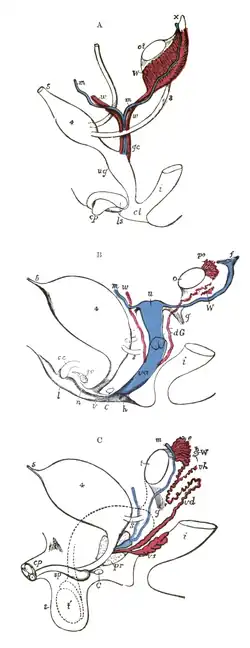

Ontogenetische Entwicklung der Vagina

Die Geschlechtsorgane entwickeln sich vor der Geburt aus einer zunächst geschlechtsunspezifischen Anlage an gleicher Körperstelle bei allen Menschen.[22] Verbunden ist die Entstehungszone der inneren und äußeren Geschlechtsorgane zunächst mit den harnbildenden Exkretionsorganen. Dabei handelt es sich um das Urogenitalsystem, dessen wesentliche Elemente im Verlauf der ontogenetischen Geschlechtsdifferenzierung die Müller-Gänge und Wolff-Gänge sind. Beide Gangsysteme sind beim Embryo anfangs links- und rechtsseitig angelegt, also paarig vorhanden.

Bei genetisch weiblichen Embryonen bildet sich der Wolff-Gang ab der zehnten Schwangerschaftswoche zurück, während sich unter dem Einfluss von Estrogenen nach und nach sowohl der Uterus und die äußeren Genitalien als auch die Vagina entwickeln. Eileiter, Uterus und das Binde- und Muskelgewebe der Vagina entstehen unmittelbar aus dem Müller-Gang.[23] Das Vaginalepithel entwickelt sich hingegen aus dem Sinus urogenitalis.[24]